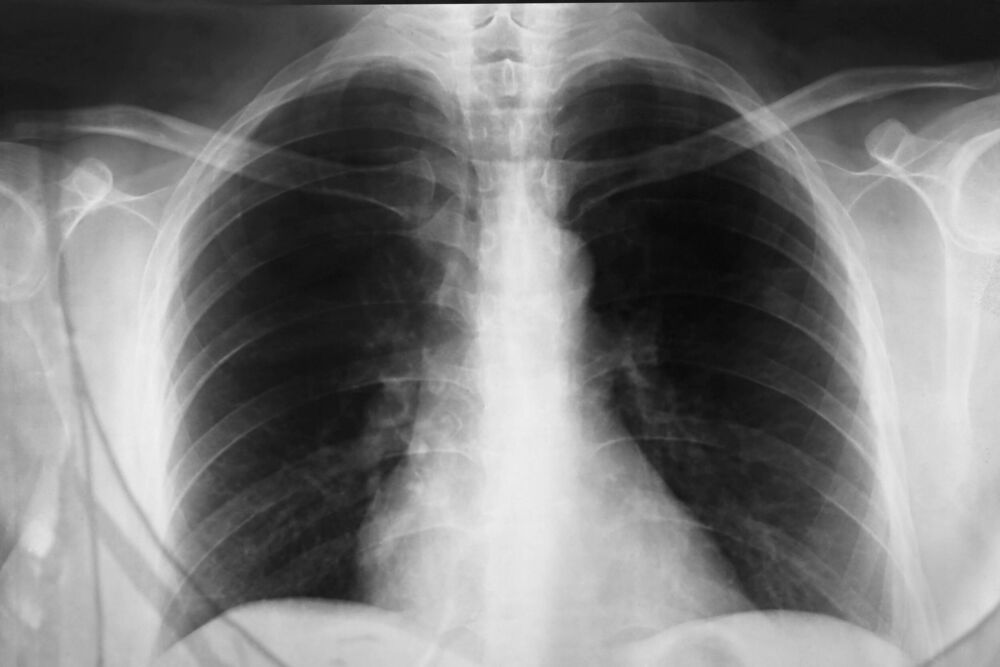

Svako ko doživljava dugotrajan ili neuobičajen kašalj trebao bi se obratiti stručnjaku, jer rana procjena može spriječiti ozbiljne posljedice. Osobito je važno obratiti pažnju na dodatne simptome poput otežanog disanja, zviždanja u grudima ili bola u prsima. Ovi simptomi mogu ukazivati na ozbiljnije zdravstvene probleme koji zahtijevaju brzu intervenciju, kao što su bronhitis, astma ili čak pneumonija. Uz pravilnu brigu, kontrolu okruženja i stručni savjet, moguće je znatno smanjiti tegobe i izbjeći komplikacije koje nastaju kada se simptomi zanemare. Uzimanje u obzir porodične anamneze takođe može biti korisno, jer određene hronične bolesti dišnog sistema imaju genetsku komponentu.